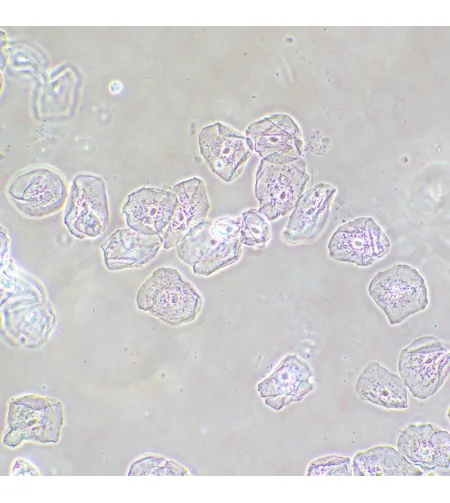

MAGUS SPH2 faasikontrastsuseadme koosneb faasikontrasti liugurite komplektist, faasikohustusega andurite komplektist ning keskendava teleskoobist. Faasikontrastsuseadet kasutatakse läbipaistvate madala kontrastsusega proovide uurimiseks, mis pole heledas väljavalguses nähtavad. Värvimine tapab elusaid rakke. Tehnika peamine eelis on see, et seda saab kasutada elusate värvimata organismide uurimiseks nende loomulikus olekus. Tehnikat kasutatakse meditsiinis, ökoloogias, farmakoloogias, põllumajanduses jne.

Faasiobjektiivid erinevad tavalistest objektiividest selle poolest, et nende väljumispupilli tasapinnal on faasiring. Tasapinnelised akromaatilised faasiobjektiivid moodustavad pilti, mille fookus on keskel ja servadel sama, seega on moonutus ebaoluline. Kroomaatilised aberratsioonid on parandatud siniste ja punaste jaoks, sfäärilised aberratsioonid - roheliste jaoks ning väli kõverus on parandatud 90% vaatevälja läbimõõdu jaoks. 10x objektiivi kasutatakse proovide uurimiseks koos kaanega või ilma. 20x, 40x ja 100x objektiive kasutatakse proovide vaatlemiseks 0,17mm kattega. 100x objektiiv toetab õli immersiooni. Objektiivid on mõeldud lõpmatu korrektsiooniga torupikkuseks. Parfokaalne kaugus on 60mm.